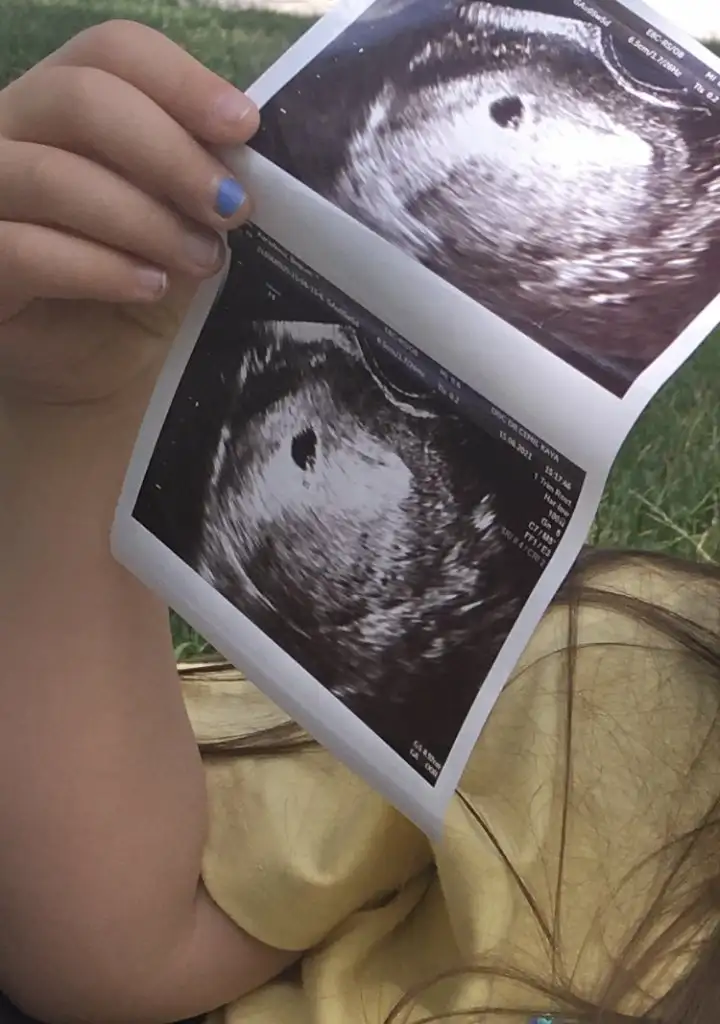

KızBana da bakabilirmisin canım 7+4 haftalik karından çekildi ultrason

Erkek gibimerhaba :) ben de ekledim fotoğrafları. ilki 5 hafta, ikincisi 9 hafta. her ikisi de karından

Böyle bir bilgi bulmuştum bugünmerhaba :) ben de ekledim fotoğrafları. ilki 5 hafta, ikincisi 9 hafta. her ikisi de karından